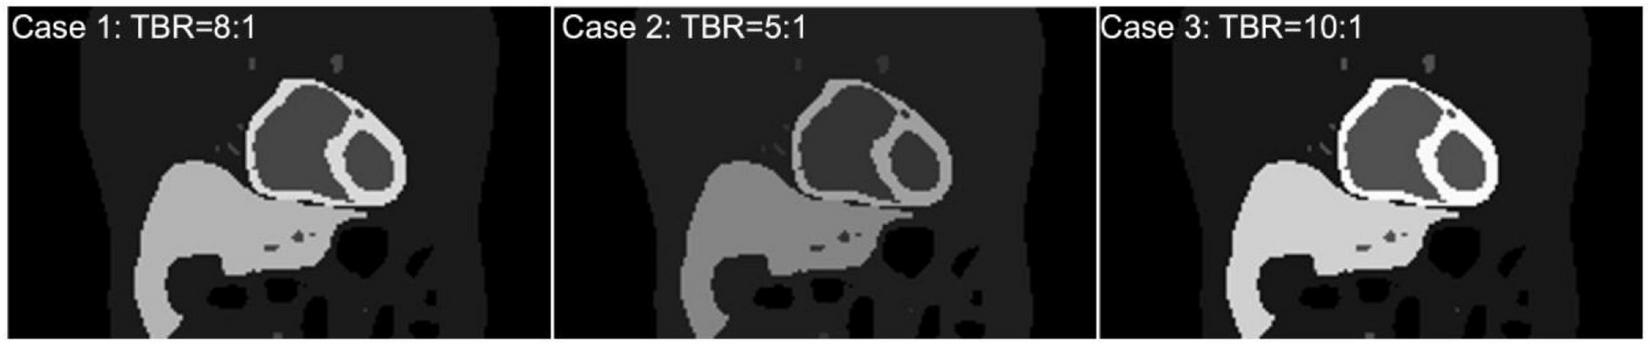

To test and validate the reconstruction algorithm, we simulated 5 different cases by modeling the TACs with different target (myocardium) to background activity ratios (TBRs) (Table 2). In all cases, we kept the total activity fixed with approximately 25 mCi at the maximum activity point in the injected dose and varied the ratios of activity of the TBR at 5, 8 and 10 at the end of the acquisition time (Case 1–3). In our simulation we considered Case 1 (TBR = 8) as the reference case for this study. Case 2 with TBR = 5 and Case 3 with TBR = 10 were considered as upper and lower bound of TBR around this reference. We have not explicitly incorporated additional noise in the simulation. However, the lower TBR corresponded to higher background activities which involved higher noise levels. Figure 4 shows the myocardial activities as a function of time for these 3 cases and Figure 5 shows the coronal views of the phantom at the end of the acquisition time (t = 360 s) corresponding to these cases.

Approximate activity distribution in the myocardium for three different TBRs: 8 (Case 1), 5 (Case 2), and 10 (Case 3).

FIGURE 5

(Top) Coronal view of the activity maps for different TBRs at time t = 360 s after the tracer injection (Case 1, 2, 3). All images were normalized by the maximum pixel value of the image with TBR = 10 (Bottom).